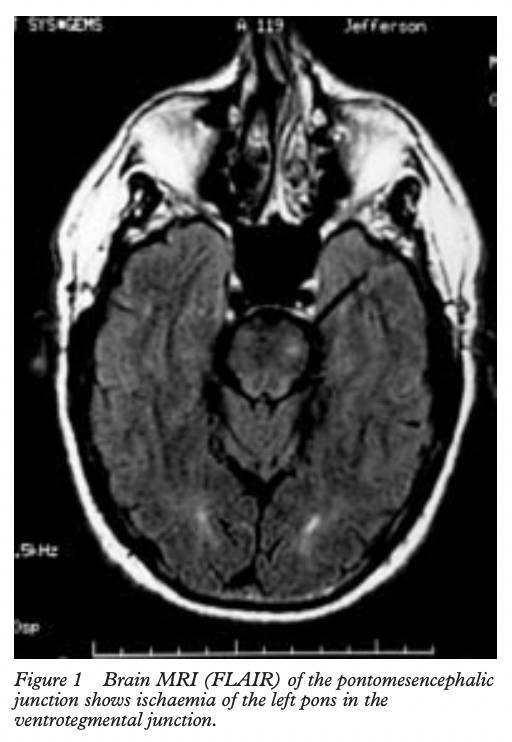

不过也有因为大脑出现罕见疾病,比如脑桥和延髓的梗塞,可能导致情感不稳定,进而无法控制大笑的情绪,结局有可能是晕厥,也有可能是死亡。

2001年一篇发表在《神经外科精神病学杂志》记载了一则罕见病例,一名65岁的男子出现了无法控制的大笑,随后短暂的右臂麻痹,同时右半边面部神经麻痹,偶尔哭泣。磁共振血管造影(MRA)和血管造影显示左脑桥和小脑小面积梗死、左椎动脉闭塞、右椎动脉和基底动脉狭窄。之后,他的病情恶化为双侧脑干梗塞,最终死亡。